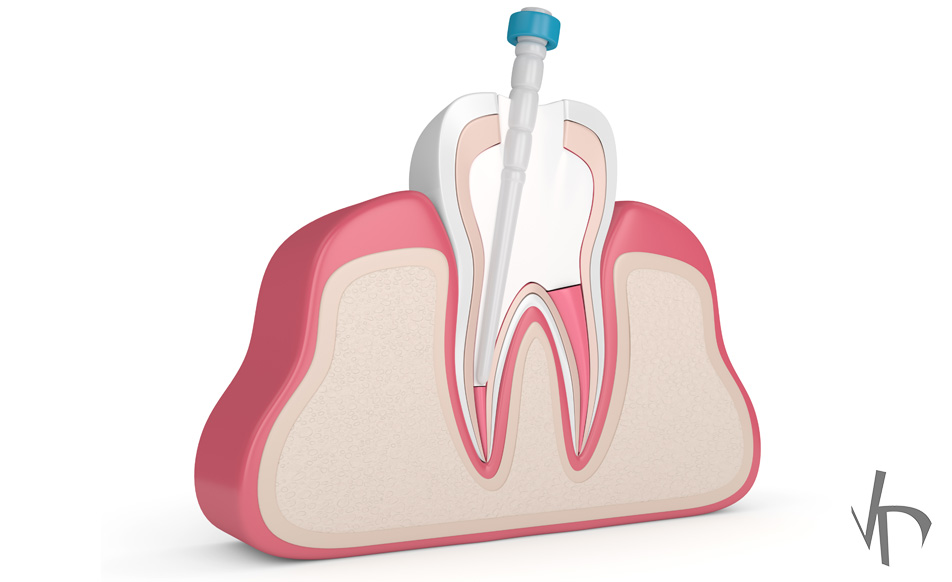

In cases where the tooth has been decayed so badly because of caviti. Use a brush with soft bristles that is small enough to fit into your. Only more recently, dentists use composites in order to create the core buildup because they act through adhesion and require a less invasive preparation.

Restore missing tooth structure with composite filling, then.